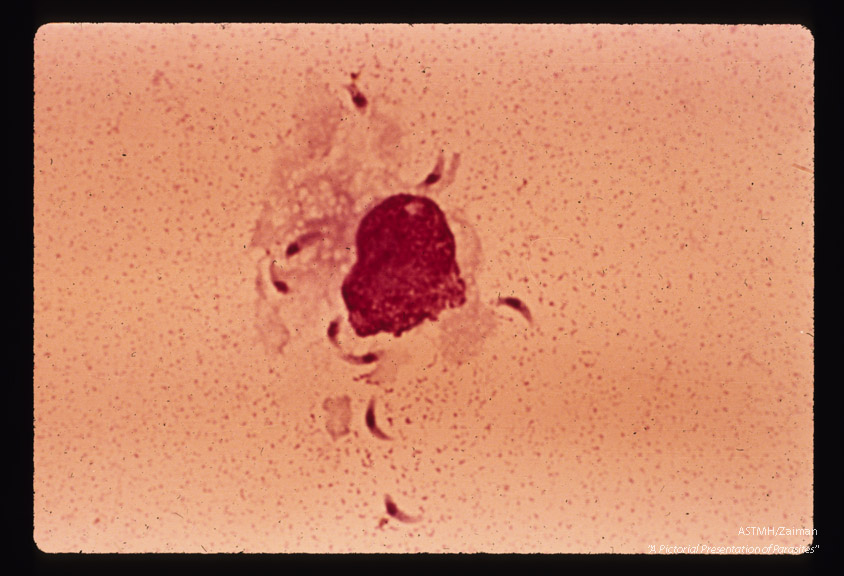

Trophic stages from rupturing cell in mouse peritoneal exudate.

Toxoplasma gondii

Description: Trophic stages from rupturing cell in mouse peritoneal exudate.